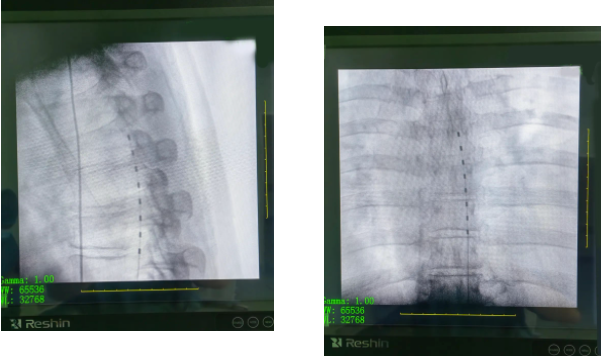

疼痛科崔家平医生接诊,通过完善相应检查、初步查体、评估后将其诊断为顽固性带状疱疹后遗症导致的神经痛。一一对症支持治疗,几天后汪某的疱疹状况有所改善,但胸壁的疼痛仍然剧烈,每天晚上只有靠打强效止痛药才能间断入睡。崔家平得知后,立即带领医护团队研究其病情根据现有病理资料经过讨论,认为患者经过大剂量止痛药物治疗欠佳,适合行神经调控技术脊髓电刺激器(SCS)植入术。经术前精心准备,在麻醉科的配合下,手术在局部麻醉下进行,患者全程保持清醒,通过调试脊髓刺激器,疼痛区域范围全覆盖一系列操作后,手术完毕效果很显著,汪某胸部疼痛症状即刻得到缓解,解除了一直困扰汪某的“大难题”。

此次手术为云南省滇东北地区首例SCS手术。此手术的顺利开展实现了医院此领域零的突破,疼痛科再创佳绩。该技术为国内较先进的治疗手段,通过微创手段(伤口0.1cm左右)将电极植入相应的责任节段脊髓的硬膜外腔,根据患者疼痛的具体情况,调整刺激脉冲发生器的脉冲参数,以达到最佳的镇痛效果,进行短时程电刺激治疗,改善急性期的疼痛症状,明显减少后遗神经痛的发生率。